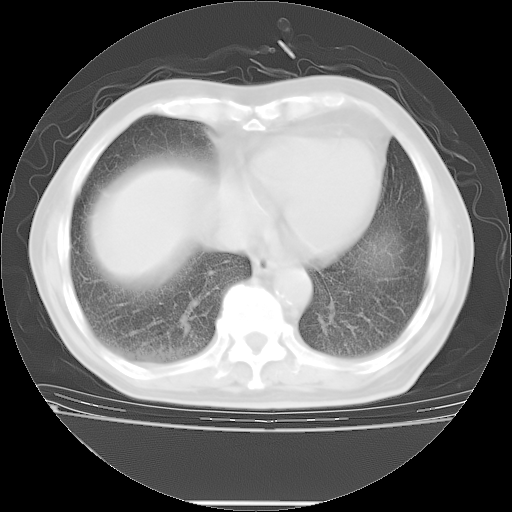

今天复查肺部CT,发现双肺广泛磨玻璃样改变。所以我把3月19日和5月9日相隔50天的肺部CT上传。请大家会诊。

5月9日肺部CT(在4月27日齐鲁医院肺部CT描述部分肺组织磨玻璃样改变,12天后肺组织广泛磨玻璃样改变)

大致读了系列胸部CT:纵隔窗无明显异常,肺窗:从4、27至今:主要是双肺中下野外带可见毛玻璃样改变,目前处于急性肺泡炎阶段,至于原因考虑1、结替组织或胶原血管性疾病所致?2、恶性疾病如恶组在肺部所致的表现或细支气管肺泡癌?3、药物或其它原因如肺蛋白沉着症所致肺泡炎目前不太可能?总之,明天就去请我院的呼吸科、感染科、血液科和临免专家会诊哈。